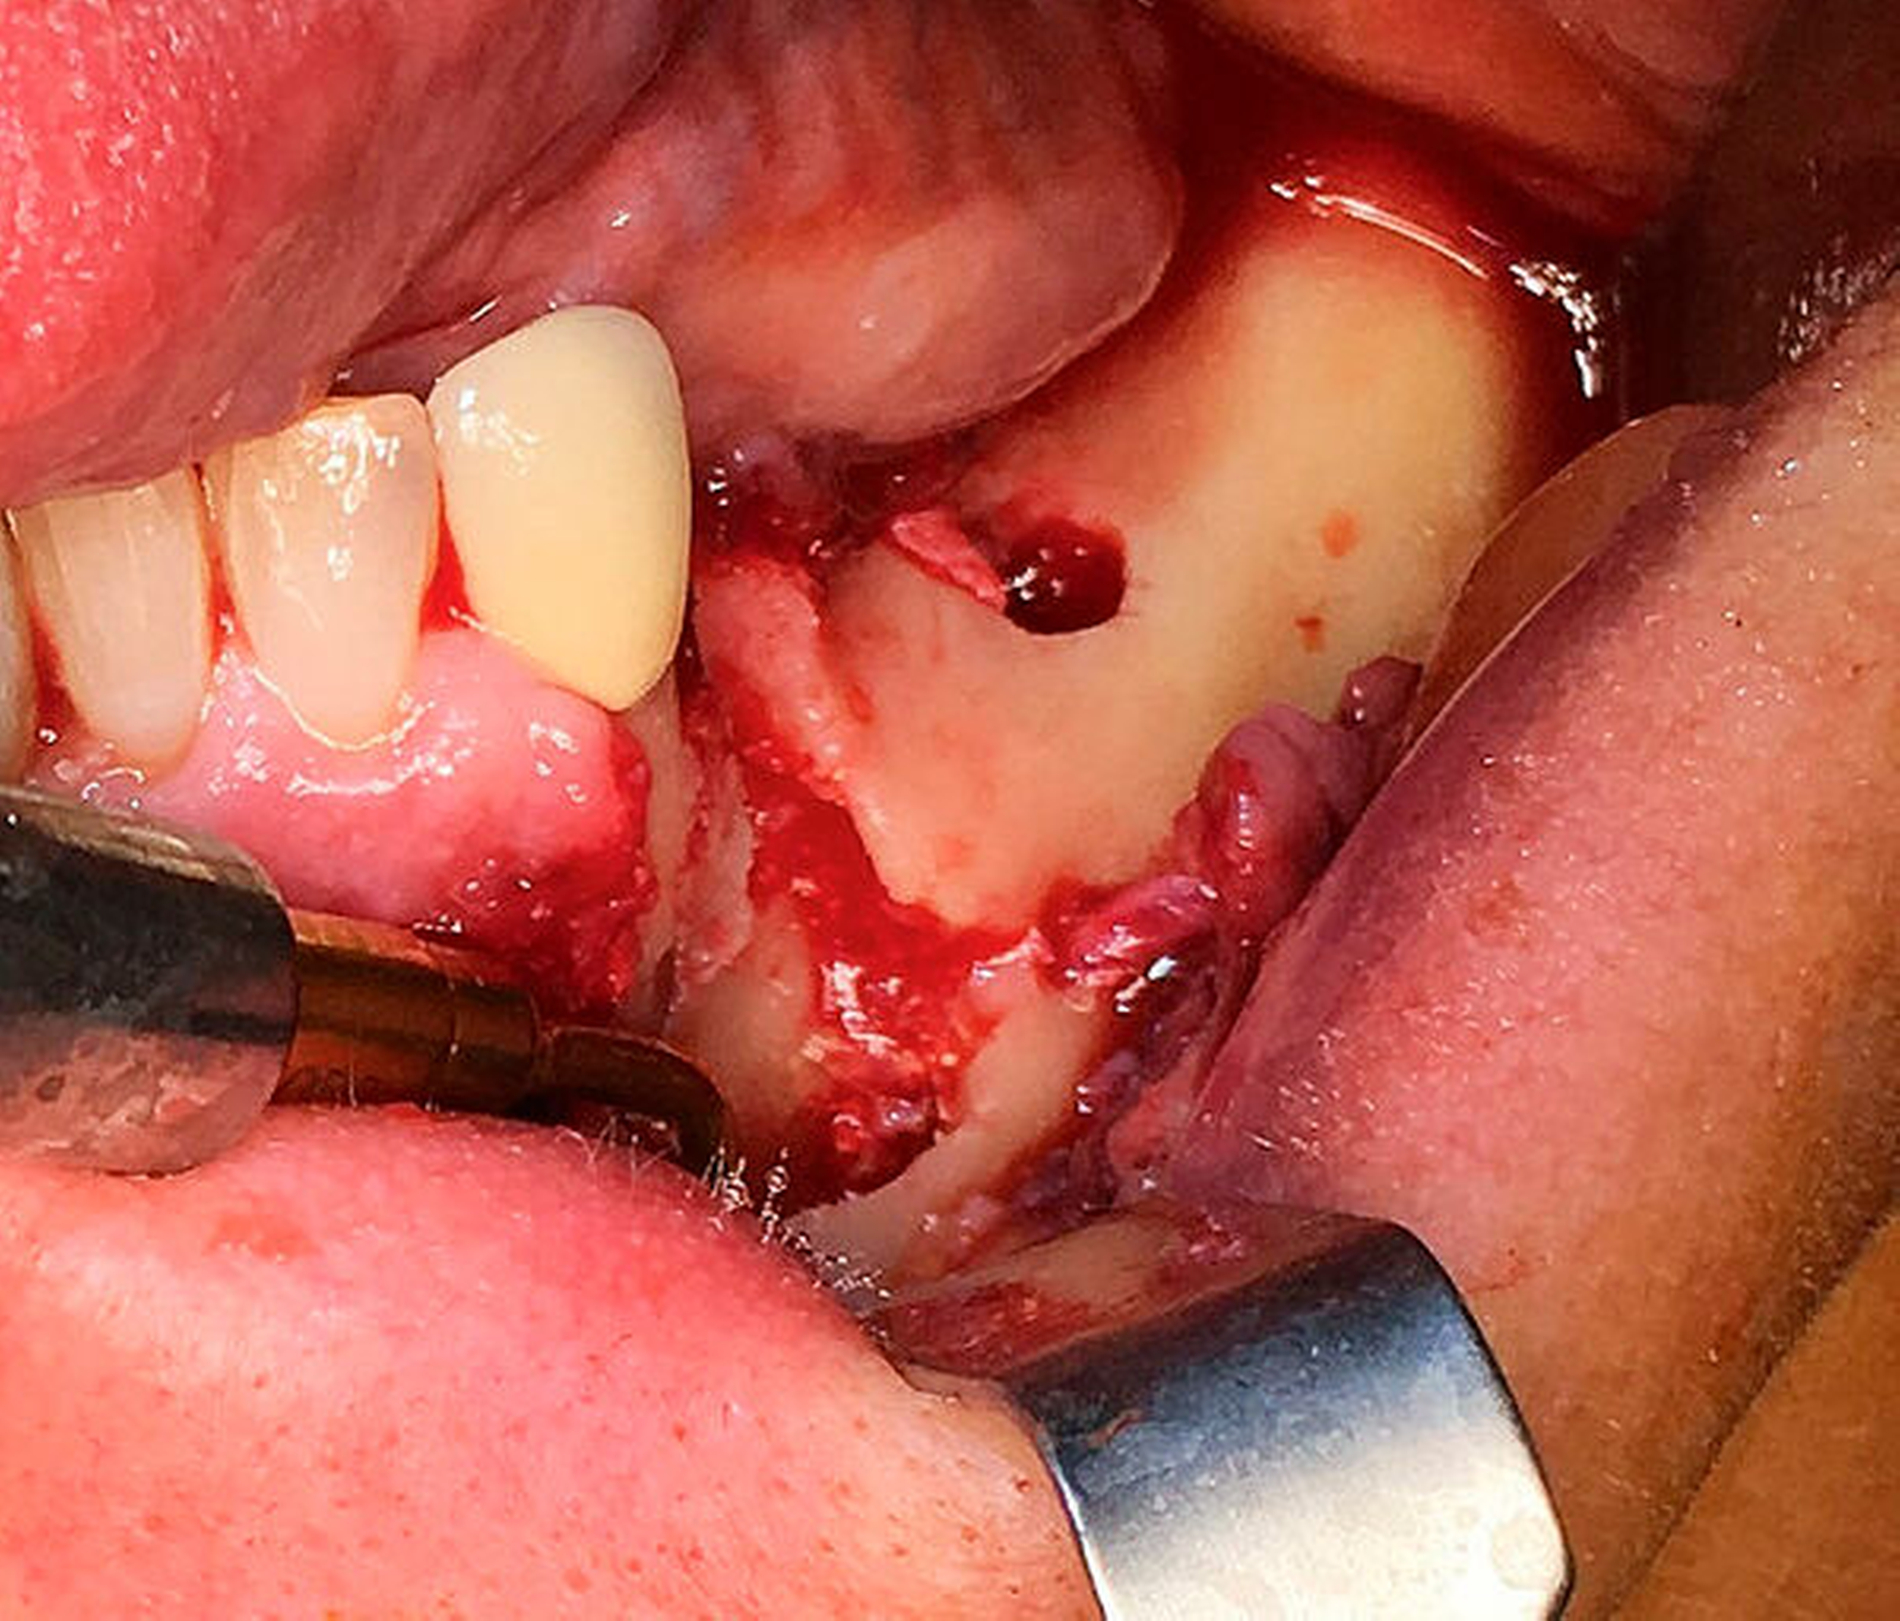

Der intraoperative Situs zeigte nach Abklappen des Mukoperiosts die Zugangskavität der alio loco durchgeführten Wurzelspitzenresektion. Der Wurzelrest 44 ist hierbei noch in situ (Abbildung 5).

Nach der Entfernung des Wurzelrests 44 wurde der Nervus mentalis am Foramen mentale dargestellt und aus dem umgebenden Weichgewebe frei präpariert (Abbildung 6). Aus der Resektionshöhle und nach Entfernung der vestibulären Knochenlamelle auch aus dem Unterkieferkörper konnte anschließend der Sealer samt der extrem weichen Spongiosa entfernt werden. Die Lage der radiologisch dichten Verschattung im krestalen Bereich regio 36 konnte ebenfalls lokalisiert und problemlos entfernt werden. Bei dem Fremdkörper handelte es sich vermutlich um einen Amalgamrest (Abbildung 7).